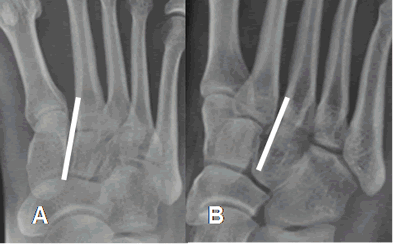

Normalmente existe continuidad entre el 2º metatarsiano y la cuña medial en la proyección AP del pie y entre el 3º metatarsiano y la cuña lateral en al proyección oblicua. (Fig 53).

Fig 53. Alineación de los metatarsianos.

A: Rx AP del pie. Alineación entre el 2º metatarsiano y la cuña medial.

B: Rx oblicua del pie. Alineación entre el 3º metatarsiano y la cuña lateral.